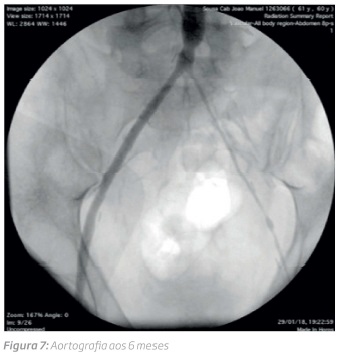

Em consulta de follow-up aos 6 meses constatou-se o aparecimento de sintomas sugestivos de claudicação intermitente. O exame eco-doppler realizado mostrou curvas monofásicas na artéria femoral comum esquerda e a angiografia (figura 7) realizada estenose difusa do ramo esquerdo (artéria femoral superficial). Foi instituído tratamento médico com melhoria clínica e aumento de distância de marcha. Os parâmetros infeciosos controlados periodicamente não revelaram alterações.